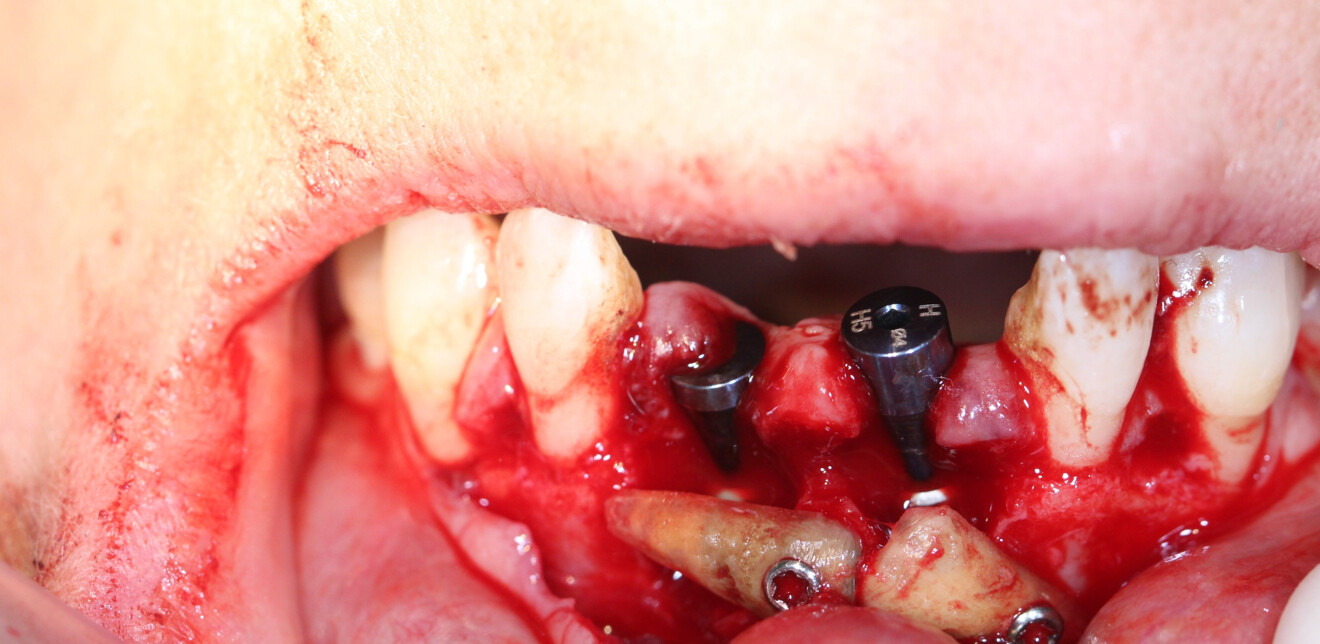

Nous réalisons un lambeau avec une incision crestale décalée en palatin en 11 et 21, sulculaire en 12, 13, 22, 23, en prenant soin de préserver les papilles interdentaires, ainsi que deux décharges verticales en distal des canines. Nous réalisons un décollement de pleine épaisseur (Figs. 28 et 29). Les dents (12, 22 et 18) sont facilement extraites et les alvéoles curetées avec soins. Deux implants (4*13) sont positionnés dans la paroi palatine des alvéoles, il subsiste une déhiscence vestibulaire en 22. Les racines de 12, 22 et 18 sont séparées dans le sens de la longueur. Les racines préparées comme indiqué ci-dessus, sont vissées en vestibulaire et en occlusal de la crête, au moyen de vis d’ostéosynthèse (diamètre 0,9 mm), afin de reconstruire la crête osseuse au niveau des inters de bridge ainsi que la paroi vestibulaire de la crête au niveau de 22 (Figs. 30 et 31). Le gap vestibulaire entre les implants et la crête ainsi que l’espace entre la crête et le greffon au niveau de 21, sont comblés avec un matériau d’origine synthétique (Collapat II Symatese). Le lambeau est tracté, suturé coronairement avec un fil tressé synthétique 5.0 (Fig. 32). Des piliers coniques droits pour prothèse plurale transvissée sont posés, et une empreinte prise à la fin de l’intervention (Fig. 33). Un provisoire est réalisé dans la journée par notre laboratoire de prothèse et posé le soir même. (Figs. 34 et 35)

Pour se faire il a été décidé d’exploiter les racines extraites (11 et 21) pour reconstruire la paroi vestibulaire des alvéoles. Nous réalisons un lambeau avec une incision sulculaire de 13 à 23, en prenant soin de préserver les papilles interdentaires, ainsi que deux décharges verticales en distal des canines. Nous réalisons un décollement de pleine épaisseur (Fig. 11). Les dents sont facilement extraites et les alvéoles curetées avec soins. Deux implants (4*10) sont positionnés dans la paroi palatine des alvéoles, il subsiste une déhiscence vestibulaire (Fig. 12). La racine de 11 est séparée dans le sens de la longueur en deux fragments. Les racines préparées comme indiqué ci-dessus, sont vissées en vestibulaire de la crête au moyen de deux vis d’ostéosynthèse (diamètre 0,9 mm) afin de reconstruire la paroi vestibulaire (Figs. 13 et 14). L’espace entre l’implant et le greffon est comblé avec un matériau synthétique (Collapat II, SYMATESE). Le lambeau est tracté, suturé coronairement avec un fil tressé synthétique 5.0 (Fig. 15). Une empreinte est prise à la fin de l’intervention, le provisoire, préparé dans la journée par notre laboratoire de prothèse est vissé le soir même (Fig. 16). L’implant 21 ayant un couple de serrage insuffisant pour être mis en fonction, il s’agit d’un provisoire cantilever, direct implant, vissé sur l’implant 11 (Fig. 17).